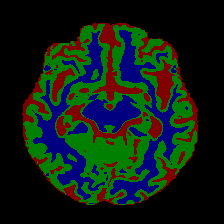

3.5 Analysis of Class Activation Maps

To further investigate the model’s decision-making process, we utilize Class Activation Maps (CAM) to visualize class-specific attention, with results presented in Figure 8. The heatmaps reveal that PCMambaNet learns to accurately localize target tissues for each class with remarkable efficiency. After only 5 epochs on limited data, our model generates clean, well-defined activation maps that focus precisely on the relevant anatomical structures. While the baseline Mamba-UNet’s performance improves with more data (e.g., 200 epochs), its activation maps often remain diffuse or highlight irrelevant regions. In stark contrast, PCMambaNet, with just 5 epochs on the same large-scale dataset, produces significantly more focused and semantically meaningful heatmaps. This superior localization ability provides strong evidence for our central thesis: the PPM effectively guides the model’s focus, while the CRN refines the representation, enabling the network to rapidly learn and generalize the intrinsic characteristics of each tissue class.

Figure 8: Qualitative comparison demonstrating the superior convergence speed and segmentation accuracy of PCMambaNet. Despite being trained for only 5 epochs, our PCMambaNet (bottom rows) produces significantly more accurate and well-defined segmentation heatmaps on both the OASIS-1 and MRBrainS13. This performance markedly surpasses the baseline Mamba-UNet (top rows), which was trained for 50/200 epochs. For each dataset, columns display heatmaps for individual classes (Background, CSF, GM, WM) followed by the final prediction overlay.